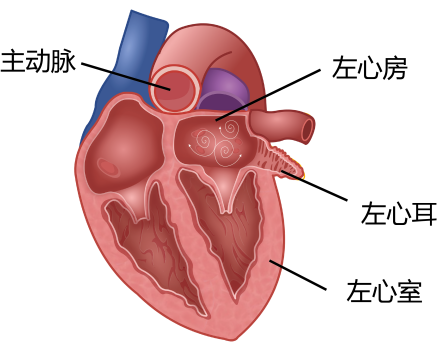

左心耳封堵是一种微创手术,手术时在心房颤动患者大腿根部血管穿刺并插入导管,进入心脏后精确定位,在左心耳入口处释放一个外表覆有膜的草莓形封堵器,封堵住左心耳,从而消除了左心耳形成血栓的隐患,达到预防脑卒中的目的(图3)。

图3.心耳造影左心耳封堵器外形与心耳对应关系